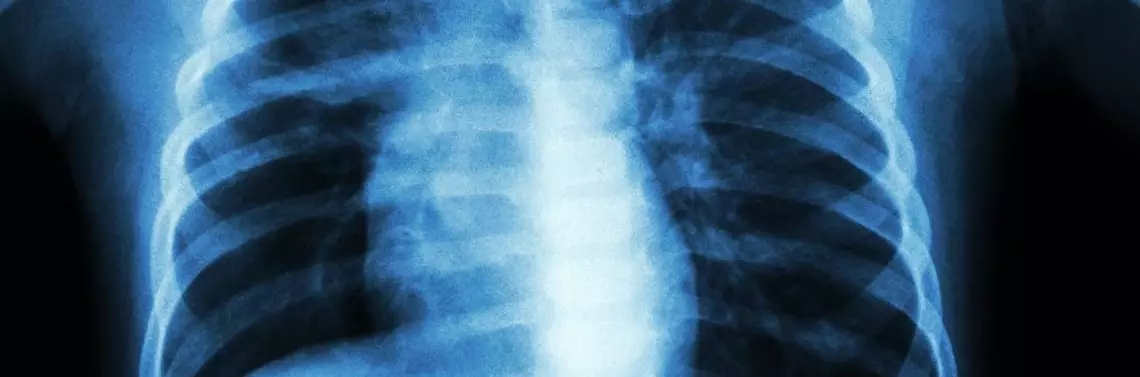

Mimo ciężkiego przebiegu choroby w badaniach laboratoryjnych wskaźniki zapalne okazały się niskie (CRP 2,98 mg/dl, PCT 0,05 ng/l), nie wykazano także odchyleń w morfologii i parametrach biochemicznych krwi, a jedynie w materiale z wymazu z jamy nosowo-gardłowej wykazano obecność antygenu wirusa RSV. W badaniu radiologicznym klatki piersiowej wykonanym w dniu przyjęcia do szpitala uwidoczniono drobnoplamiste zagęszczenia okołooskrzelowe przywnękowe z komponentą zagęszczeń konsolidujących w polu górnym prawego płuca [ryc. 1]. W badaniu laryngologicznym nie stwierdzono odchyleń od normy.